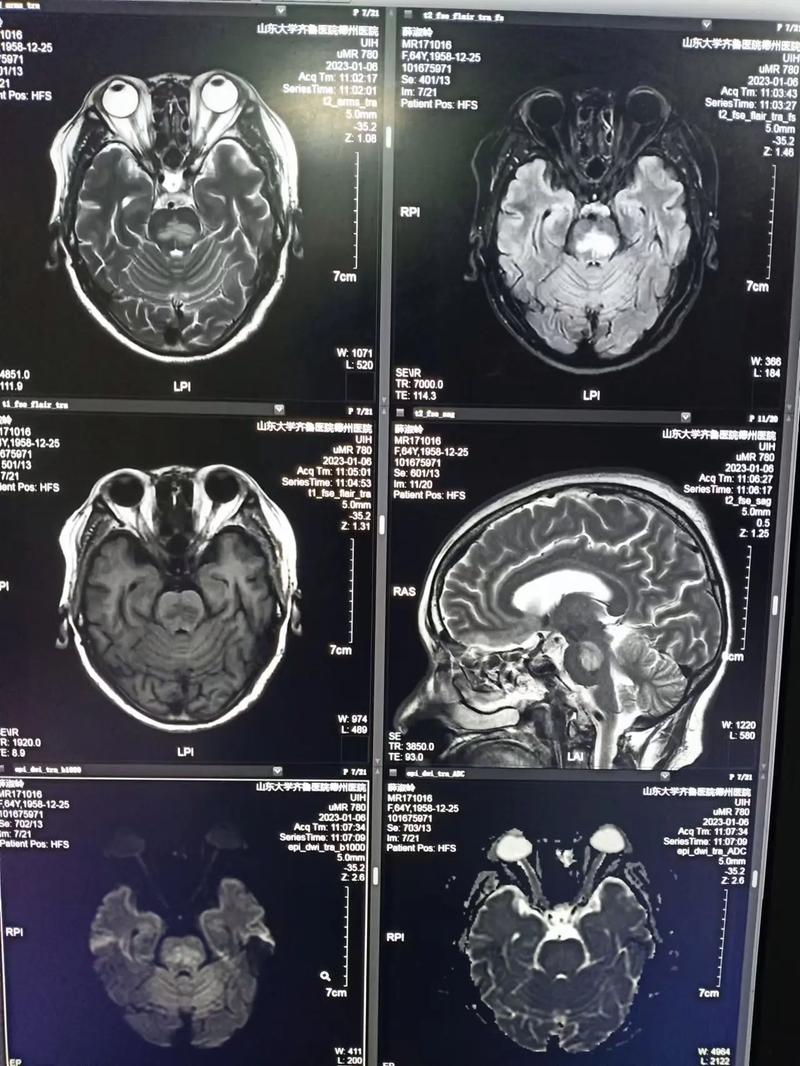

(图片来源网络,侵删)

(图片来源网络,侵删)- CT通常显示正常。 这是CT诊断脑梗最大的局限性,在发病最初的几个小时内,脑细胞刚刚开始死亡,但整个脑组织的含水量变化还不足以在CT图像上形成明显的密度差异,医生可能会根据临床症状高度怀疑脑梗,但CT结果正常。